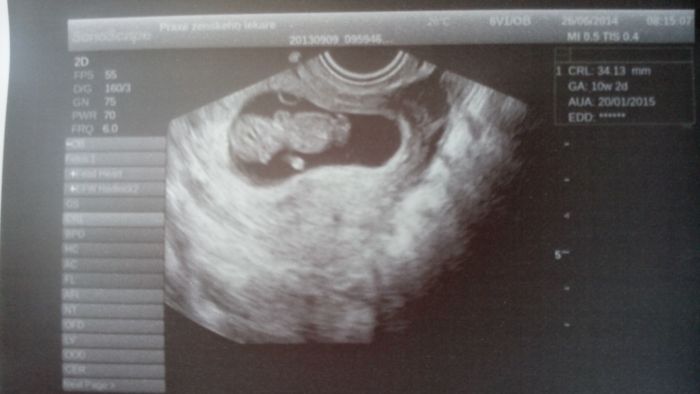

Sari, my jsme podle kalendáře byli včera na kontrole 10+0, ale právě podle velikosti cca 3,7 jsme 10+4. Fotečky jsem si prohlížela i zpětně, všechny jsou krásné!